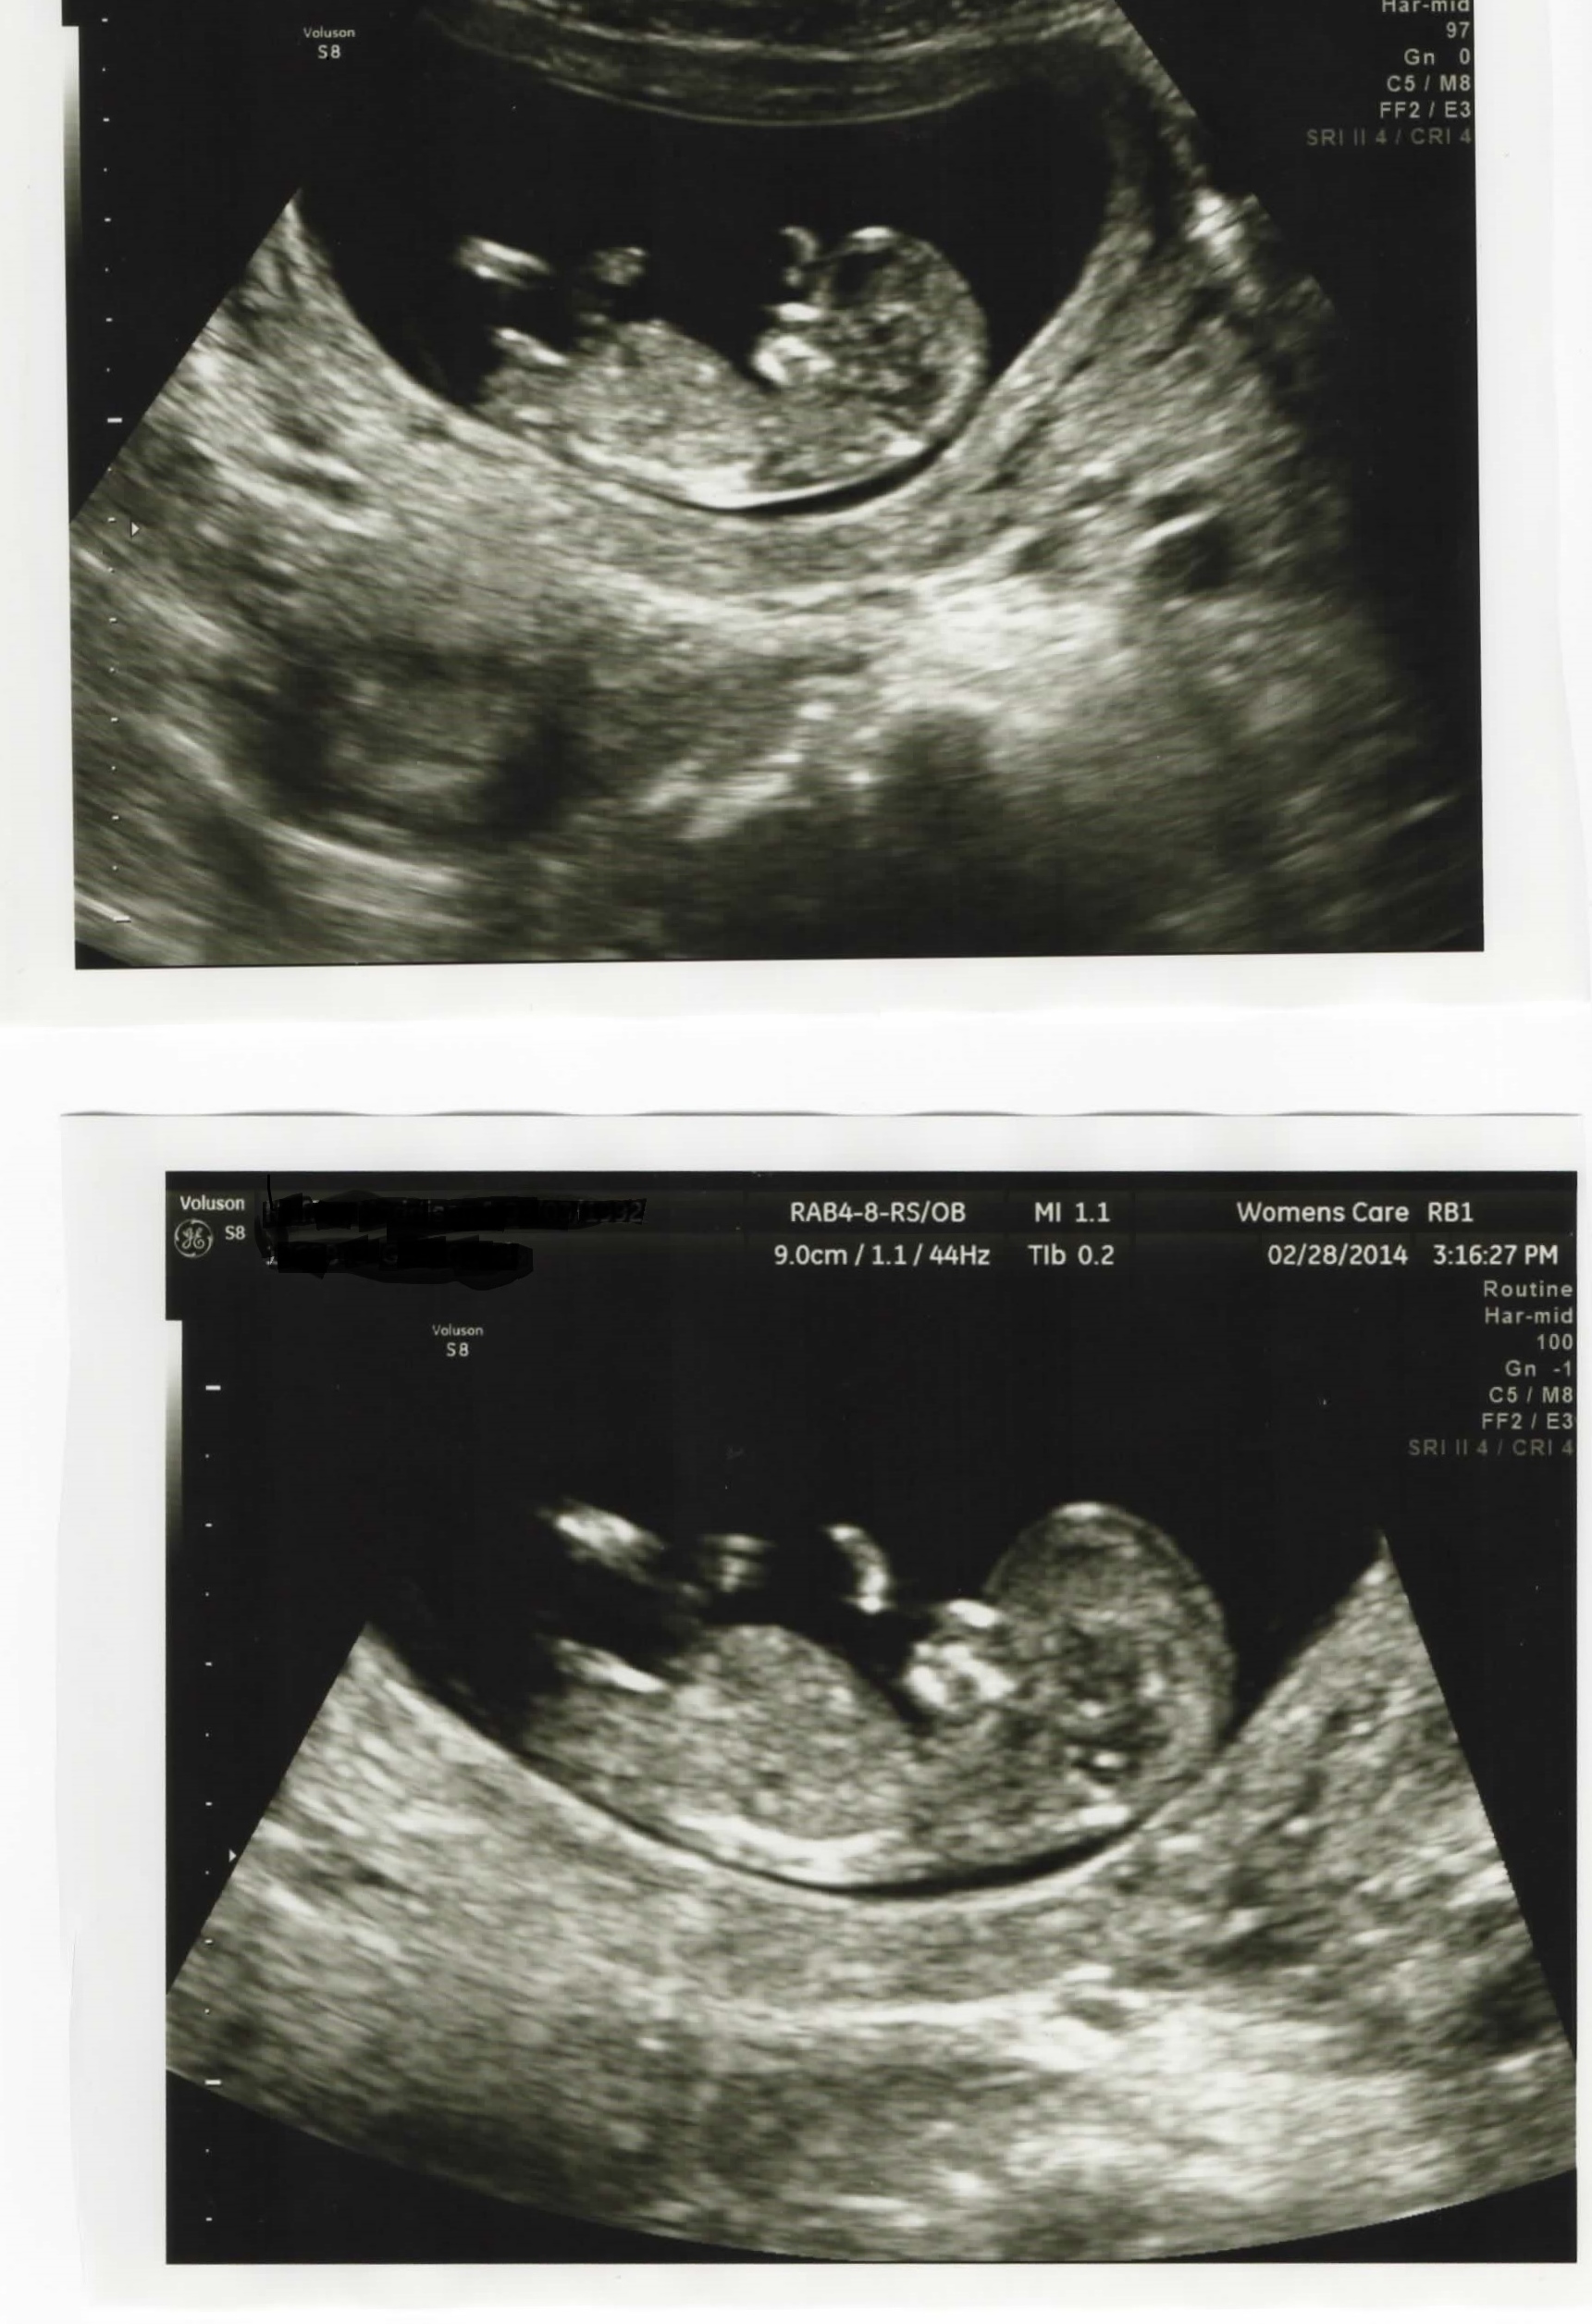

Nub guesses please!

Hi this is my first post here! I just had my first scan yesterday and the tech said she thinks it looks like a girl! We spent 10 minutes getting good shots of the nub! Anyways it seems kinda long and big? And im having some doubts =/ Attachment 17261Attachment 17262

In the second pic it looks like a split in the end of the nub..... Oh and 11 weeks 6 days!

is it normal for a girl nub to be so thick and long?

Girl- they do tend to be longer than boy nubs. It's very flat now but there is potential to rise since it's still early. Would guess girl though 60/40